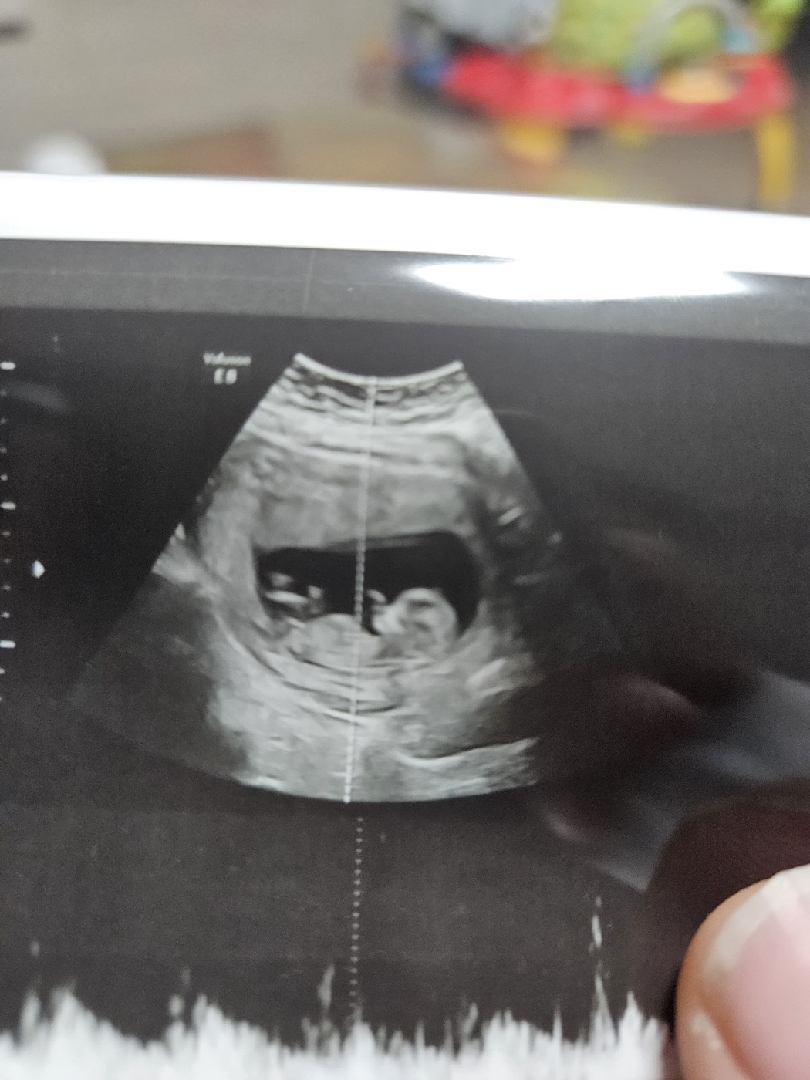

둘찌초음파

아들일까요?딸일까요?

아직 성별을 알기엔 좀 이른 크기 인것같아요...ㅋㅋㅋ 저 허연거 탯줄 같아보이는데.. 둘째라니 대단하시네요..!!

아들아닌가요?^^;